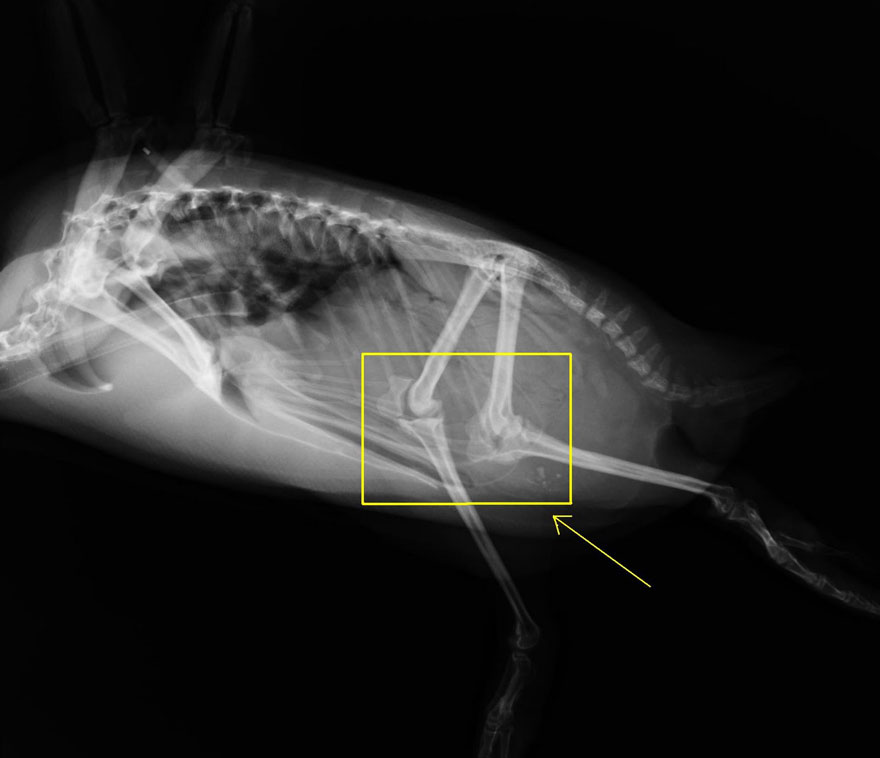

ROMA – Anche i pinguini hanno le ginocchia. Questi adorabili animali, hanno le stesse ossa delle gambe presenti nella maggior parte dei vertebrati bipedi. A differenza però degli altri vertebrati, parte di queste ossa sono coperte dalle piume.

Gli scienziati hanno stabilito che ai pinguini camminare costa molta più energia rispetto ad altri animali terrestri e hanno concluso che questo ha favorito il loro adattamento e la loro mobilità sott’acqua. In effetti, i pinguini sono dei veloci nuotatori eccezionali, che si nutrono di prede che vivono tutte sott’acqua.